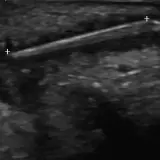

Over 2,100 interactive radiology cases, curated by radiologists for your level of training. Scroll, window, and view cases full screen — just like on PACS. Click linked findings in each writeup to jump straight to them on the image. Cases include sample reports, a focused discussion section, original illustrations, and videos.

Casos totalmente interactivos con las herramientas que esperaría de un PACS: scroll, ventana, zoom, pan, mediciones, ROI y modo de pantalla completa.

• Anotaciones enlazadas

Anotaciones extensas resaltan los hallazgos clave directamente sobre los casos. Haga clic en los hallazgos enlazados dentro de la descripción del caso para saltar a su ubicación exacta en el estudio.

Desplace, arrastre, ajuste ventana y amplíe como en una estación PACS de trabajo

Aprenda con eficiencia gracias a hallazgos de imagen anotados e ilustraciones